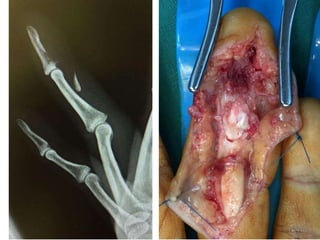

Zone 1

• Leddy type I – treat within 3 weeks

• type II and III treatable even after 6 weeks.

• Ultrasound helpful in locating the proximal

stump.

• Microsuture anchors or ORIF if bone fragment

• Ensure tendon-bone contact before final knot-

tying.

• Too tight repair - quadrigia.

• > Two-strand repair techniques

Leddy Packer Type III